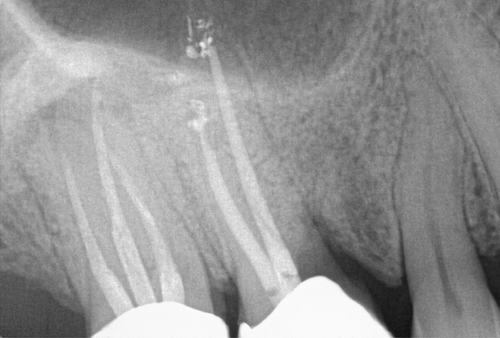

Successful Root Amputation

Resorption

Resorption is a condition where the tooth’s structure starts to break down, either from the inside out or from the outside in. It can be caused by trauma, inflammation, or other factors. Endodontic treatment for resorption involves removing the damaged tissue and reinforcing the tooth with materials that help prevent further damage. The aim is to save the tooth and maintain its functionality as much as possible.